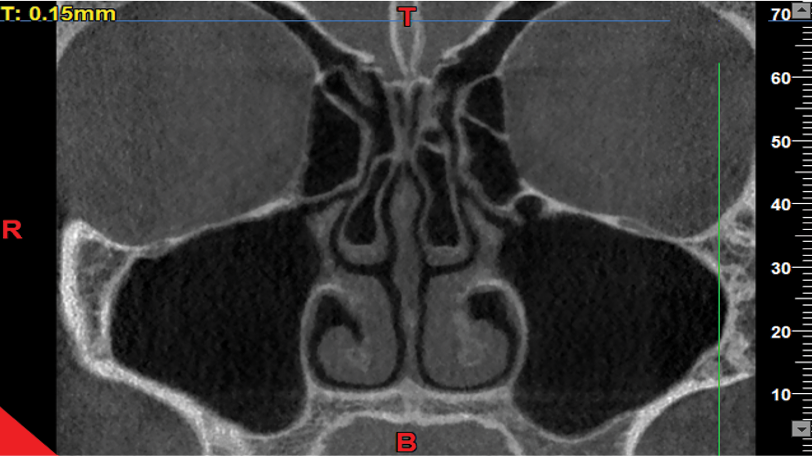

The axial, coronal, and sagittal views were used to assess the presence/absence of concha bullosa (Figure-1), and to measure the infundibulum length and ostium height (the most reliable and commonly used view to identify concha bullosa and make the measurements is the coronal view). The reviewed images visualized both the maxillary sinuses and the nasal cavity. Images with poor quality and those not visualizing the sinus floor, showing complete obstruction of the ostium, or lacking the middle concha were excluded. The patients’ age and gender, presence/absence of right and left concha, infundibulum length, and right and left ostium height were all recorded. The CBCT scans were evaluated by a board-certified oral and maxillofacial radiologist with 20 years of clinical experience. Subjectivity of the measurements was a source of bias in this study. To verify the reliability of the measurements, the intra-examiner reliability was calculated by repeating the measurements after a 3-month interval. The intraclass correlation coefficient was calculated to be 95%, indicating excellent intra-examiner reliability. To measure the dimensions of the drainage system, the infundibulum length and the ostium height were measured on both sides. For this purpose, the coronal view was scrolled to select the cross-section in which the uncinate process and the path of infundibulum and ostium were clearly visible, had an open path, and the largest values of the length and height were measured. The maximum length and height could be found on one or two different cross-sections. The infundibulum length was considered as the distance between the center of the ostium and the highest point of the uncinate process [3] (Figure-2). The ostium height was considered as the distance between the center of the ostium and the lowest point of the floor of the maxillary sinus [3]. To measure this variable, a line was drawn tangent to the lowest part of the sinus floor and parallel to the horizon. Next, a line was drawn perpendicular to the above-mentioned tangent line from the center of the ostium, and the obtained height was recorded (Figure-3).

Figure 2. Measuring the infundibulum length